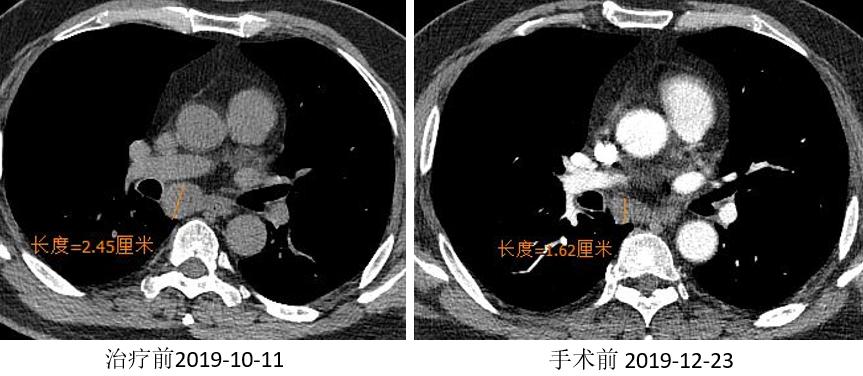

胸部CT

外周淋巴结CT

2019.01.03 行“VATS辅助左肺下叶切除术”。

术后冰冻病理:(左下叶)见少量异型细胞,病灶内见纤维组织伴淋巴组织增生、组织细胞聚集、胆固醇结晶沉积及反应性多核巨细胞,结合病史符合新辅助治疗后反应(MPR)。(第11组淋巴结)肺组织内见纤维组织增生伴炎细胞浸润及组织细胞反应。

疗效评价:MPR。